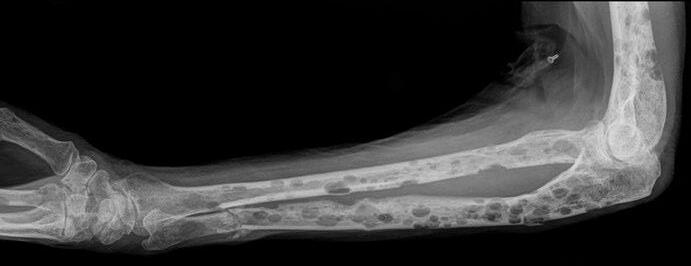

Conventional X-rays reveal punched-out lytic lesions, osteoporosis, or fractures in 75% of patients.

FDG PET/CT appears to be more sensitive (85%) than skeletal survey for the detection of small lytic bone lesions.